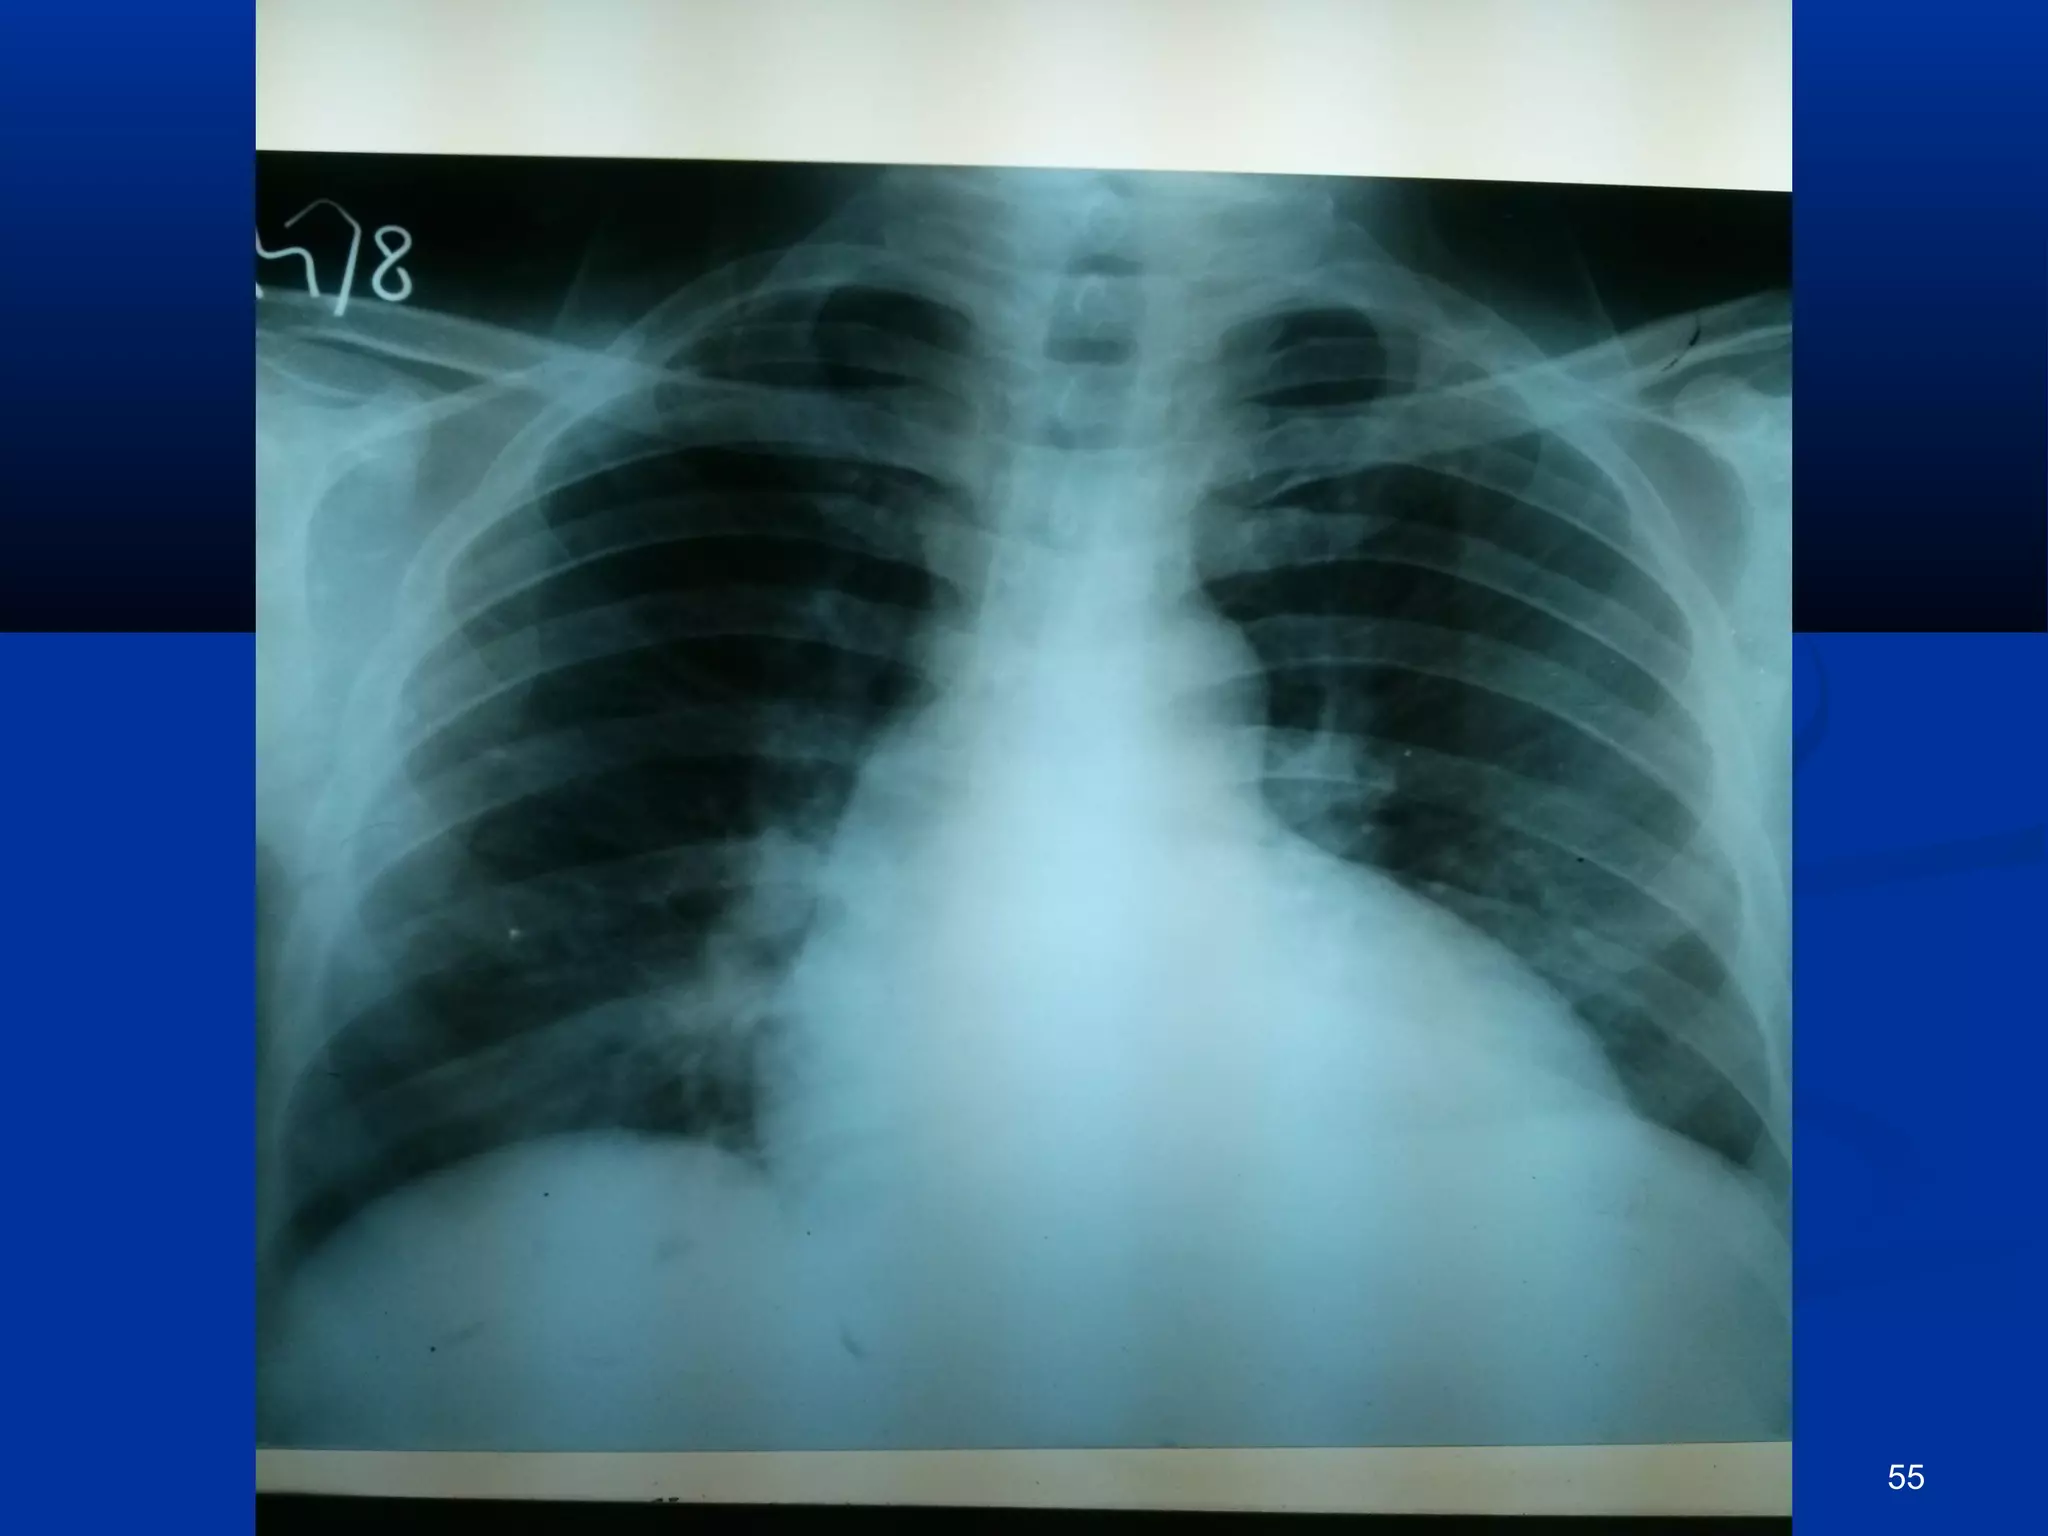

CCXXRR--PPAA

CCXXRR-PPAA .. FFiinnddiinnggss ooff ppuullmmoonnaarryy eeddeemmaa rreessoollvveedd 54

pprrooggrreessss  HHeeiiss aaffeebbrriillee && AAccttiivvee  SShhoorrttnneessss ooff bbrreeaatthh sseettttlleedd  RRtt.. SSiiddeedd WWeeaakknneessss iimmpprroovviinngg  LLeefftt ppoosstt.. ttiibbiiaall aarrtteerryy ggoott jjuusstt ppaallppaabbllee.. DDoorrssaalliiss ppeeddiissuuss nnoott ppaallppaabbllee yyeett.. ppaaiinn iinn lleegg iimmpprroovveedd.. lleevveell ooff ccoollddnneessss iinn lleefftt lleegg ddeeccrreeaasseedd ttoo lloowweerr 11//33rrdd RRFFTT’’ss ggoott bbaacckk ttoo nnoorrmmaall.. CCXXRR-PPAA .. FFiinnddiinnggss ooff ppuullmmoonnaarryy eeddeemmaa rreessoollvveedd 54